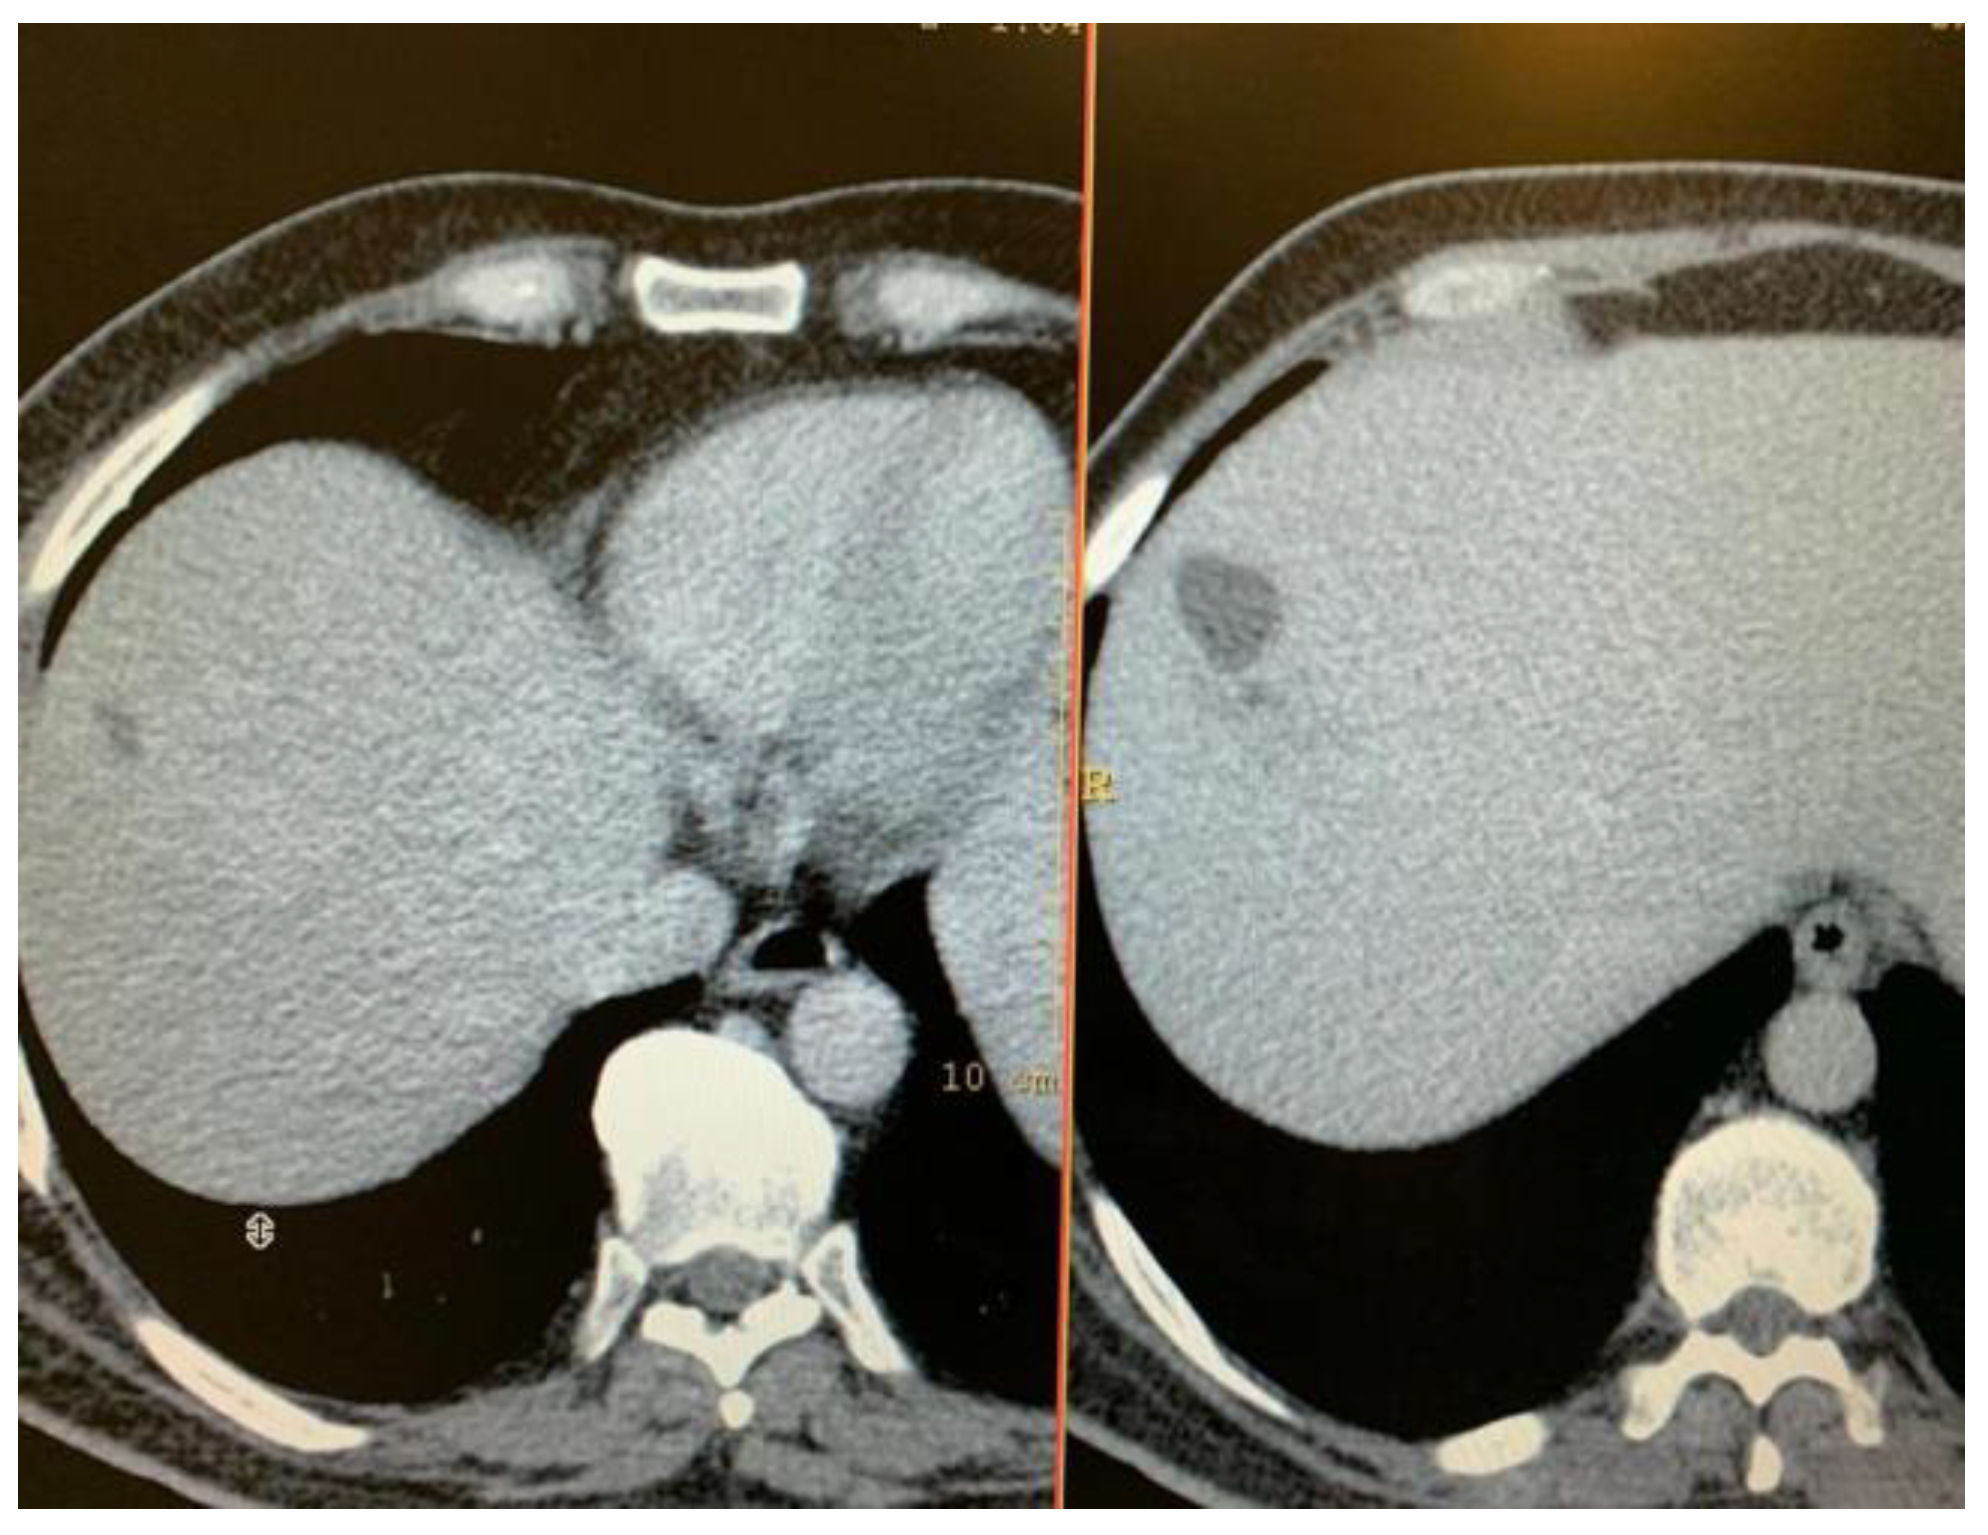

Thoraco-abdominal computer tomography was performed to identify the focus of the primary infection, in a patient with no other organ specific symptomatology. A multiloculated, non-homogenous hepatic abscess located in the right lobe, segment VIII, of 50/32/57 mm diameter, surrounded by a hypodense area. The paraclinical data confirmed the general inflammatory syndrome, with and ESR (12 mm/h), leukocytosis 15.7/30*3/microL with neutrophilia 84.2%, and showed mild increase of hepatic enzymes: AST (85UI/L), GGT (113 UI/l). Blood culture were obtained, but could not identify any pathogenic agent. IG ELISA for Echinococcosis was negative. Infectious disease and general surgery evaluation recommended empiric general antibiotherapy was initiated with intravenous Ceftriaxone 1 g/day, switched after 5 days to meropenem 1g at 8 hours and Vancomycin 1 g at 12 hours for, for 14 day. Progressive remission of the hepatic liver abscess was observed on serial computer tomography (Figure 4).

Figure 4.

Serial CT exam: diminished size of the right lobe hepatic abscess: a) after intravenous therapy; b) at admission.